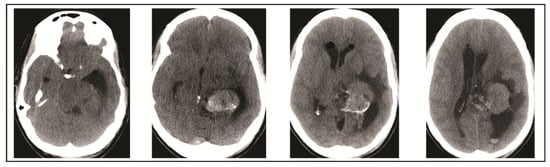

2. Case Presentation